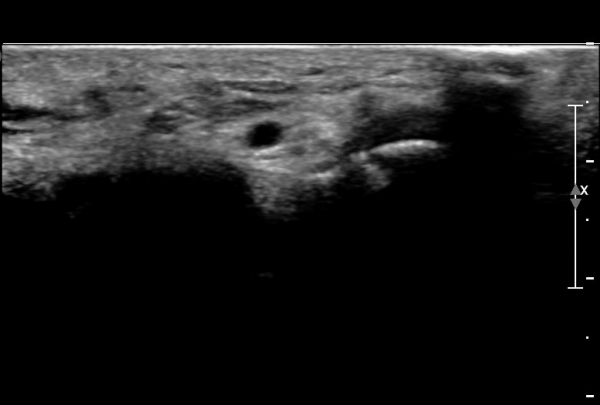

ŽÃËÀÚ¸¦ ¾à°£ ¸»´ÜÀ¸·Î À̵¿ÇÏ´Ï ¿¬ºÎÁ¶Á÷ ºÎÁ¾ÀÌ ´õ¿í ½ÉÇÏ°Ô °üÂûµÇ°í(»çÁø 2),

Á¶±Ý ´õ ¸»´ÜÀ¸·Î À̵¿ÇÏ´Ï Äá¾Ë»À ÇÇÁú°ñ ¿¬¼Ó¼º ¼Ò½ÇÀÌ °üÂûµÊ(»çÁö 3),

Äá¾Ë»À Á¾´Ü¸é°Ë»ç¿¡¼­ Äá¾Ë »À ±ÙÀ§ºÎÀÇ ÇÇÁú°ñ °ß¿­ÀÌ °üÂûµÊ(»çÁö 4).